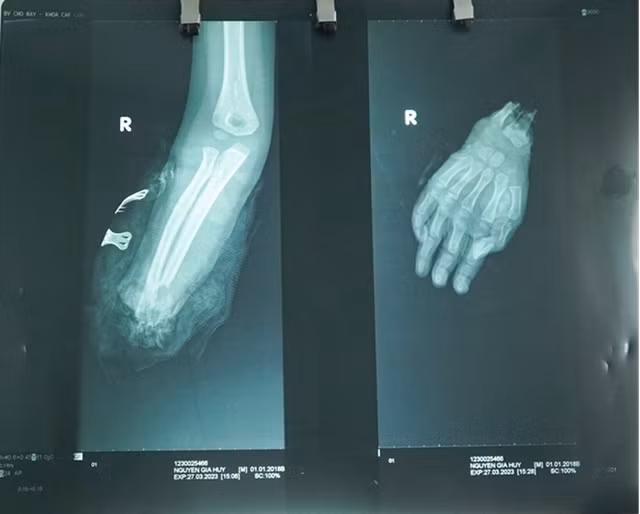

| Phim chụp X-quang cánh tay bị đứt lìa của bệnh nhi H. |

Người nà bệnh nhi cho biết, bé đang đi bộ thì bị xe gắn máy đụng phải dẫn đến đứt lìa bàn tay phải. Sau khi sơ cứu tại địa phương, bé được chuyển đến cấp cứu tại Bệnh viện Chợ Rẫy.

Theo BS CK1 Nguyễn Phước Bình, Khoa Chấn thương chỉnh hình, tại Bệnh viện Chợ Rẫy, bệnh nhân đã được phẫu thuật cấp cứu (với sự tăng cường của đội ngũ bác sĩ về vi phẫu) nối lại bàn tay đứt rời, nối lại xương, mạch máu, gân, cơ, dây thần kinh bàn tay…

“Với một đứa bé chỉ mới 5 tuổi, cấu trúc cơ, xương hay các bộ phận khác chưa phát triển hoàn chỉnh, mạch máu rất bé… nên mọi công đoạn phẫu thuật gặp nhiều khó khăn. Tuy nhiên, với sự cố gắng và nhiều kinh nghiệm của các bác sĩ chuyên khoa, ca phẫu thuật đã thành công”, BS CK1 Nguyễn Phước Bình chia sẻ.

Ca phẫu thuật kéo dài hơn 7 giờ. Hiện tại, các dấu hiệu sinh tồn của bệnh nhi ổn định, dịch ở vết mổ cẳng bàn tay đã khô, bàn tay cũng hồng ấm và các ngón tay đã vận động nhẹ. Dự kiến, bệnh nhân sẽ được xuất viện vào tuần sau.